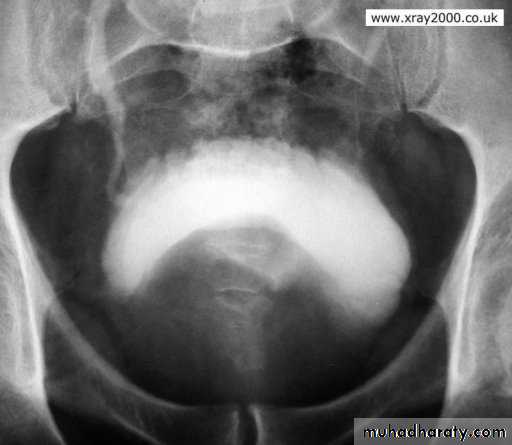

U/S:TRUS: BPH, vesical stone, residual urine and hydronephrosis.

IVU

Vesical stone BPH